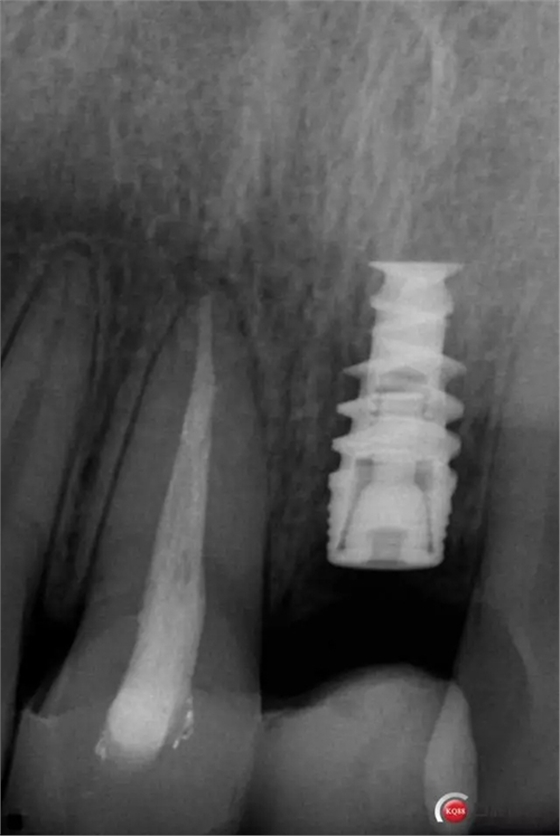

種植后修復,我們要把握每一個細節(jié),比色,轉(zhuǎn)移桿的就位,我們必須把臨床做好,技工師傅才會給我們做出好的修復體,減少一些不必要的失誤,首先術前的檢查是必要一步 ,再是器械的準備使我們臨床操作有條不紊,術前拍照,o-bite取咬合記錄,消毒修復術區(qū),旋出愈合基臺,生理鹽水沖洗袖口,拍照袖口,安放合適轉(zhuǎn)移桿,拍X線見轉(zhuǎn)移桿就為良好,硅橡膠取模,術后旋回愈合基臺,拍照比色。

藻酸鹽對頜取模,超硬石膏灌注。發(fā)加工廠,與技工溝通注意事項,等修復體做好后,檢查模型。是否就位,是否密合,預約患者復診戴牙,消毒修復區(qū),旋出愈合基臺,定位器指導安放修復基臺,試戴冠,調(diào)磨鄰接及 咬合至合適,拋光,患者滿意,加力扳手加力至30N,拍X片見就位良好,特芙蓉及暫封膏封中央螺絲孔,聚羧酸鋅粘固劑粘固,或是樹脂水門汀粘固,清理多余粘結(jié)劑,光固化樹脂封螺絲孔,拋光。術后注意隨訪。